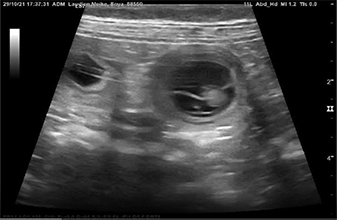

Heute war also der Tag der Tage. Der Tag an dem man Gewissheit bekommt, ob die Hündin aufgenommen hat oder nicht.

Auch wenn in den letzten Tagen einiges für eine Trächtigkeit gesprochen hat, so wollten wir es gerne

von unserer Tierärztin absegnen lassen.

Beim Ultraschall wurden auf Anhieb einige Fruchtanlagen gesichtet. Die genaue Anzahl wollte ich aber nicht wissen.... ein bisschen Spannung soll uns und den Welpeninteressenten schon noch in den kommenden Wochen erhalten bleiben.  |

Wir freuen uns einfach riesig darüber, dass bald kleine K-Racker den Bagalutenhof besetzen werden.